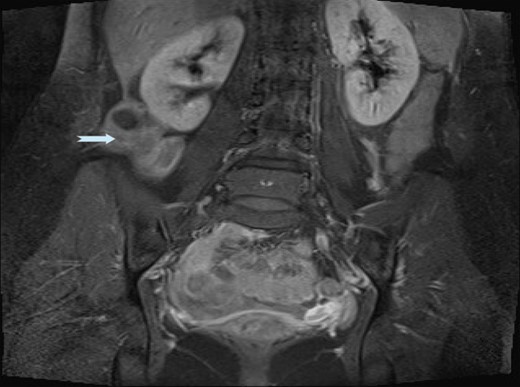

An ultrasound scan (USS) was performed and a 9 cm mass was demonstrated. A subsequent computer tomography (CT) scan confirmed the mass (Fig. 1) and raised the possibility that the mass may be a small bowel neuroendocrine tumour. The mass reported as separate from the appendix and caecum and no evidence of appendicitis. On the following day, the images were presented, the case was discussed at the colorectal multi-disciplinary team (MDT) meeting and a collective decision was made to perform a magnetic resonance imaging (MRI) scan which the patient underwent the following day. MRI was performed to specifically define the anatomy of the small bowel and its relation to the mass, as this was not clear on CT imaging. Ultimately, the MRI demonstrated a mass with vascular pedicle arising from the inferior aspect of the right hepatic lobe and the appearance raise the possibility of an exophytic liver lesion which has undergone torsion (Fig. 2). She was taken for a diagnostic laparoscopy the next day however given the size of the mass and the slim body habitus of the patient, a decision was made to convert to lower midline mini laparotomy.

CT imaging demonstrating a 9 cm lesion in the right iliac fossa, displacing adjacent small bowel.